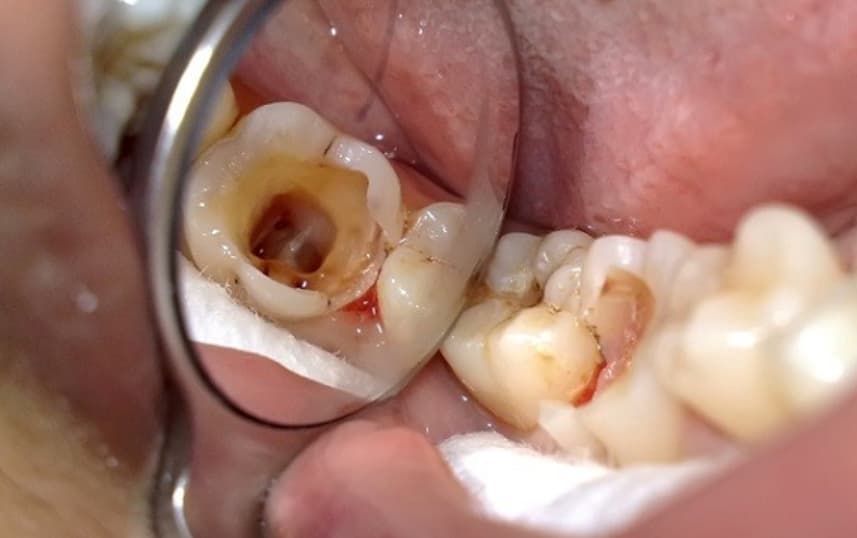

Sâu răng nặng là tình trạng sâu răng đã phát triển nghiêm trọng gây tổn thương sâu vào cấu trúc bên trong bao gồm cả lớp ngà và tủy răng. Nếu không được điều trị kịp thời răng có thể bị viêm tủy, nhiễm trùng lan rộng và thậm chí mất răng vĩnh viễn.

(Sâu răng nặng khi không điều trị kịp thời có thể gây mất răng vĩnh viễn)(**)

(Răng sâu vỡ nhiều gây khó khăn trong việc mài cùi và phục hình răng)(**)